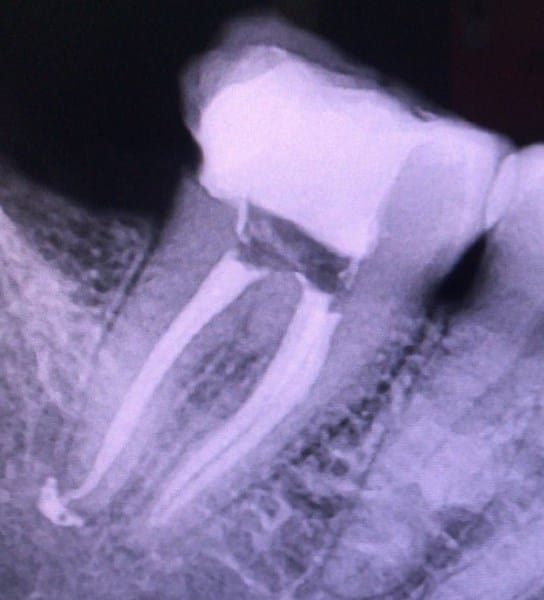

Bueno es que en el procedimiento endodontico(hace más de 3 semanas) hubo intrusión de material de obturación, lo cual me esta provocado mucho dolor desde entonces y por lo tanto he decidido sacármela porque ya no quiero pasar por más procesos para "salvar" la muela estoy cansada... Entonces opte por esta opción pero mi preocupación es que con la extracción no se solucione el problema y me siga el dolor, ¿con la extracción el material excedente también saldrá por completo?... Me urge la respuesta pues mañana tengo programada la extracción.